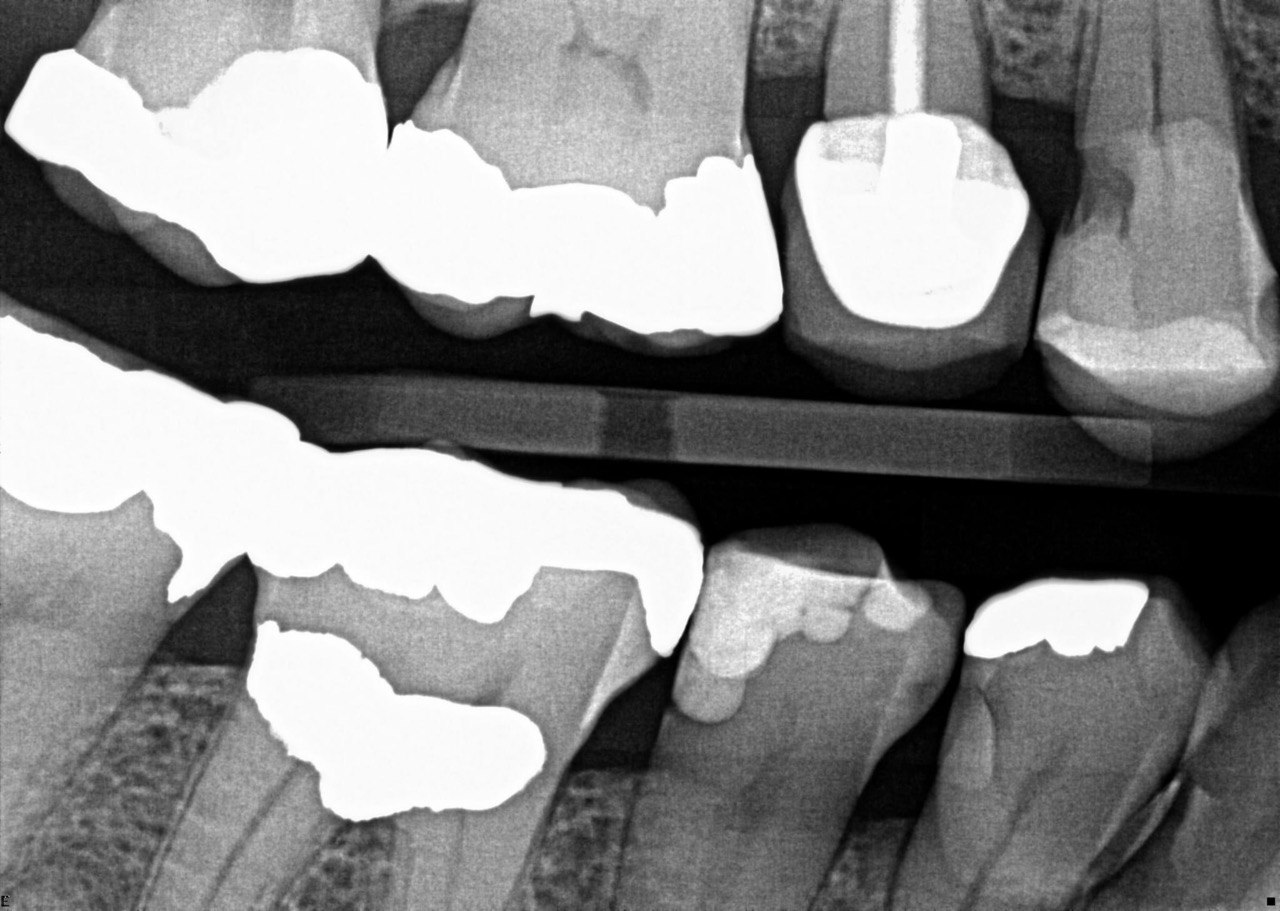

31. What option cannot be selected for the tooth # 3.6?

32. What options cannot be seen in the print of this X ray?

33. What options cannot be seen in the print of this X ray?

34. What option can be selected for tooth # 4.6?

35. What options cannot be selected for the tooth # 1.5?

36. What options cannot be selected for the tooth # 3.7?

37. What options can be selected for tooth # 1.2?

38. What option can be seen in the print of this X ray?

39. What options can be selected for the print of this X ray?

40. What cannot be seen in the print of this X ray?